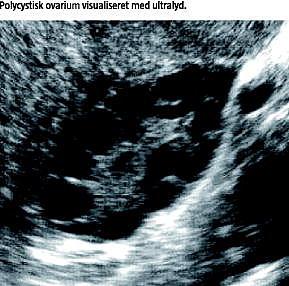

Polycystisk ovariesyndrom (PCOS) er den hyppigst forekommende endokrine lidelse blandt kvinder i den reproduktive alder med en prævalens på 5-10%. PCOS er samtidig den hyppigste årsag til infertilitet hos kvinder [1].

PCOS blev tidligere betragtet som en udelukkende gynækologisk lidelse med karakteristiske ændringer i ovariemorfologi og funktion. I dag fremviser tilstanden foruden anovulatorisk infertilitet og hyperandrogenisme også en metabolisk profil, der øger risikoen for type 2-diabetes (T2D), hjerte-kar-sygdomme (HKS) og endometrie-cancer [2].

De i dag anvendte diagnostiske kriterier for PCOS (Tabel 1 ) blev udfærdiget af The Rotterdam ESHRE/ASRM-Sponsered Consensus Workshop Group 2003 som et kompromis mellem den tidligere foretrukne europæiske diagnostik med hovedvægt på ultralyd og de diagnostiske principper i USA, hvor man tilskrev kronisk anovulation og biokemiske ændringer større klinisk betydning [3].